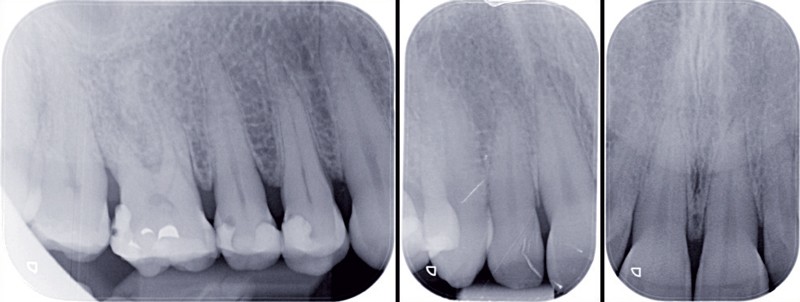

À l’examen radiographique, nous observons, surtout, une alvéolyse modérée généralisée compliquée par des lésions inter-radiculaires de classe I [3] sur 36 et 46 et des lésions carieuses sur les prémolaires maxillaires (fig. 2).